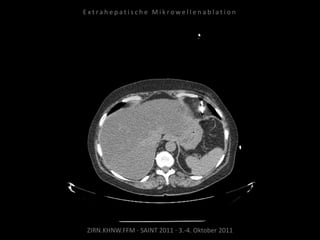

Ausgangsbildgebung:

CT vom 21.12.2009

Patient: Männlich, 74 Jahre

Diagnose: Malignes Melanom,

Metastasierung lokal begrenzt

(3 peritoneale Metastasen).